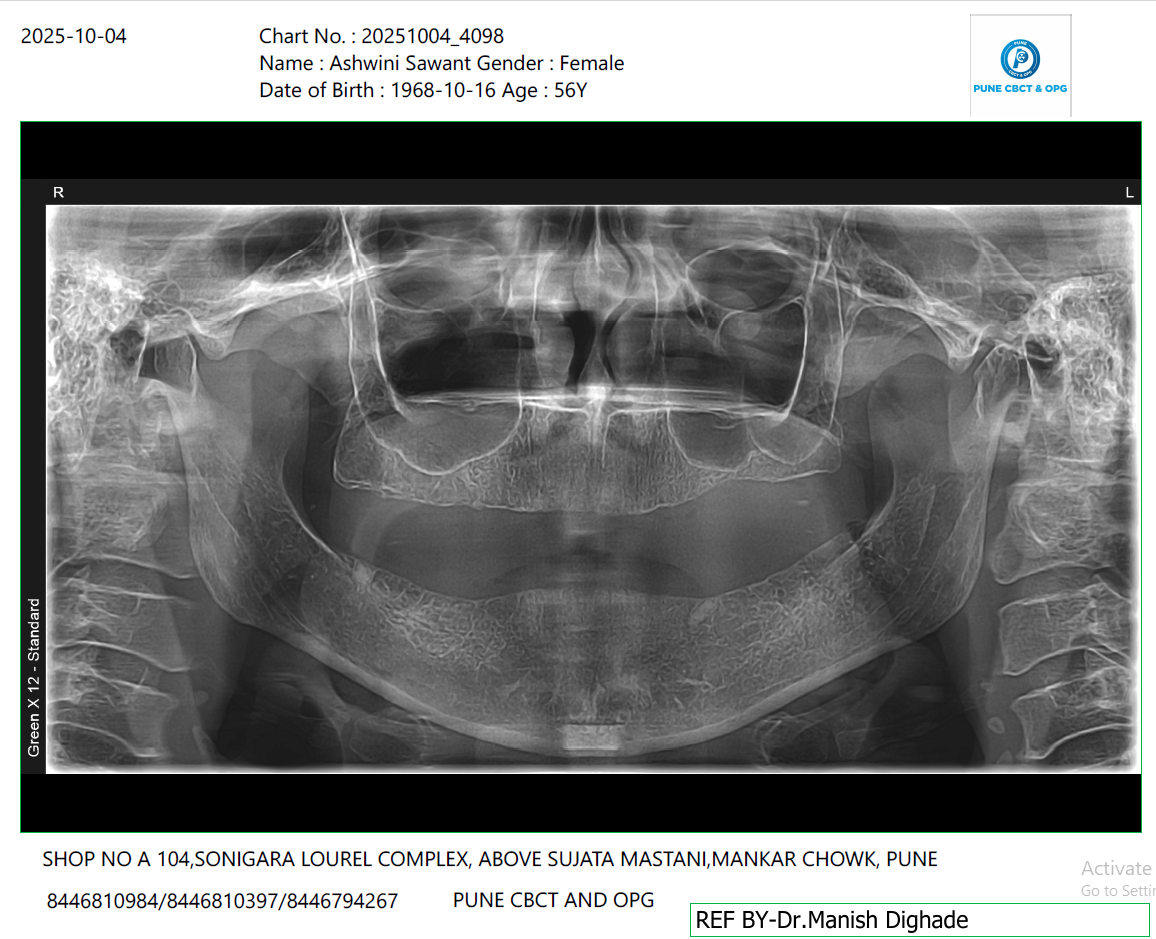

X-Ray Analysis

OPG — Before

Radiographic Findings

The post-treatment OPG shows well-placed implants in both upper and lower jaws, providing strong support for fixed prosthesis. This confirms successful implant placement and immediate loading capability.